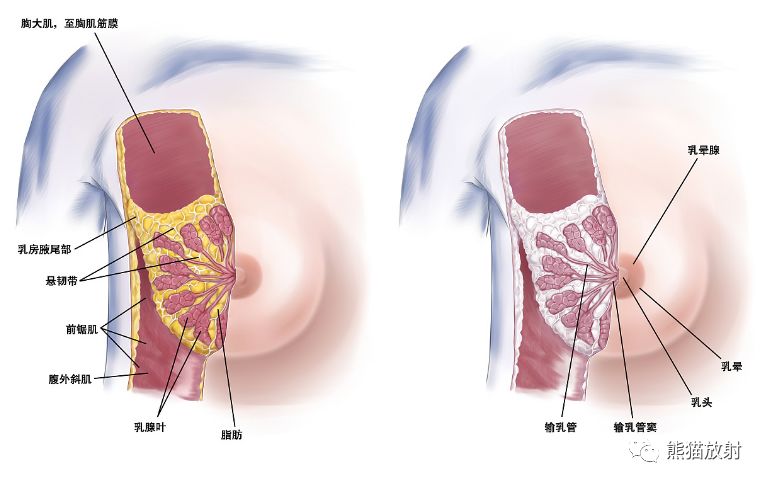

乳腺 解剖